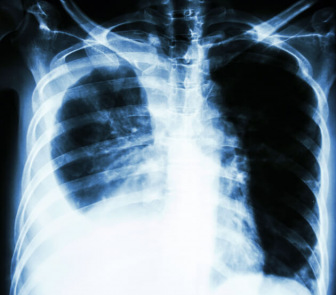

Imaging scans can show signs of pleural effusion.

Doctors use X-rays, CT scans and MRIs to look for pleural thickening. Finding it early can help guide better treatment and improve outcomes.

Doctors use the same imaging scans for pleural thickening and mesothelioma. On chest X-rays, pleural thickening shows as a thick white line along the lung’s edge. PET scans and MRIs help tell pleural thickening apart from mesothelioma.

CT scans provide detailed images showing the extent of thickening. These scans help catch problems early so treatment can start sooner.